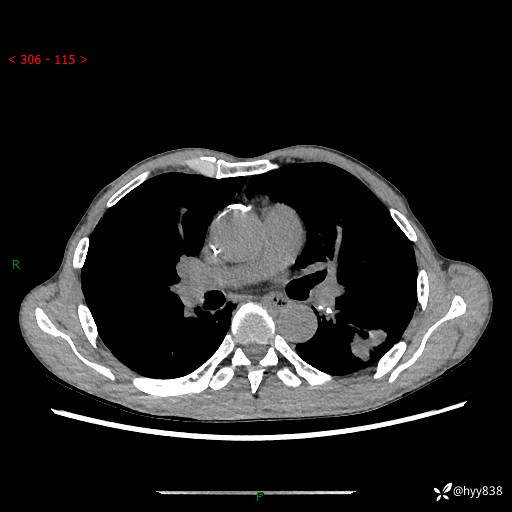

现病史:患者于1月余前无明显诱因出现背部疼痛不适,无明显咳嗽、咳痰、胸闷、咯血、发热等不适,后于2024.5.3至当地市人民医院行胸部CT示:左肺下叶结块,大小约2.2cm*2.6cm,双肺多发小结节,双肺感染性病变,部分纤维增值灶,慢支并双肺局限性肺气肿,肺大泡,纵隔淋巴结增大并部分钙化,冠脉区及大血管壁钙化,双侧胸膜局限性增厚;后口服莫西沙星2周。2024.6.12复查胸部CT示:左肺下叶结块影形态较前饱满,较大截面范围约2.8cm*2.3cm,边缘可见细短毛刺及分叶,性质待查。现患者为求进一步诊治来我院,门诊以“肺占位”收入我科。 起病来,患者精神、食欲、睡眠尚可,大小便正常,体力体重轻微下降。

胸部CT平扫+增强

各期CT值:48hu 100hu 78hu